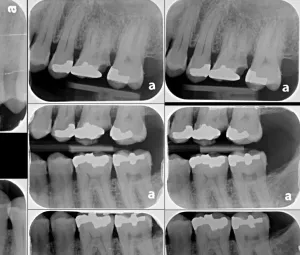

It amazes us how well people can heal sometimes. This case, done by Dr. Wes Parker, involved a 45 year old male who was referred for a carious, necrotic (dead) tooth #14 (upper left first molar). The patient also reported left sided sinus pressure and drainage. At his consultation, we obtained a Cone Beam CT (CBCT) scan. On his CBCT, you could see where the infection and inflammation from tooth #14 had eroded through the floor of the left maxillary sinus. We discussed this with him and scheduled surgery shortly after the consultation. Dr. Parker removed tooth #14, cleaned out the pus and inflamed maxillary sinus lining through the socket. The inflamed, thickened sinus lining went almost up to the orbit (eye socket). Dr. Parker then closed off the sinus communication. Following this, Dr. Parker placed a bone graft over the sinus closure, and then sutured over that to close the wound. The patient healed very well. He was compliant with the sinus precautions and medications that were prescribed. Next, Dr. Parker proceeded with implant placement in the #14 site with a simultaneous indirect sinus lift or “sinus bump.” The implant placement surgery went well, and after about 5 months of healing time, the patient received a crown on the implant from his dentist. Image #1 is a preoperative PA radiograph of the carious, necrotic, nonrestorable tooth #14 (upper left first molar). Image #2 is a coronal slice from the patient’s preoperative CBCT showing the necrotic tooth #14 with a periapical radiolucency and maxillary sinus inflammation stemming from the necrotic tooth. Image #3 is a sagittal slice from the patient’s preoperative CBCT showing the necrotic tooth #14 with a periapical radiolucency and maxillary sinus inflammation stemming from the necrotic tooth. Image #4 is a sagittal CBCT slice from the patient’s post extraction CBCT showing resolution of the sinus inflammation and measurements for the future dental implant. Image #5 is an immediate postoperative PA of the implant in the #14 site following implant placement with a simultaneous indirect sinus lift. Image #6 is a 5 month postoperative PA showing the healed, integrated implant prior to crown placement with a healed sinus lift bone graft above it and no sinus inflammation.